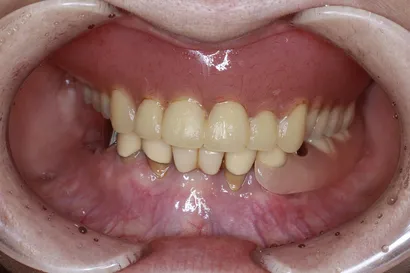

重度虫歯からの全顎インプラント治療

70代 男性

執刀医 Dr.大杉 治療内容 虫歯・歯周病が原因で噛み合わせが崩壊していたので、全顎的なインプラント治療を行い、口腔機能の回復を行いました。

上顎:ピンクポーセレンを用いたフルジルコニアインプラントブリッジ

下顎:奥歯=ジルコニアインプラントブリッジ、前歯=ジルコニアクラウン治療期間 1年6ヶ月 費用 上顎:420万 税抜

下顎:330万 税抜リスク セラミックのすり減りを防ぐために、ナイトガードを作成しています。毎晩使用することで、セラミックを長持ちさせることができます。 -